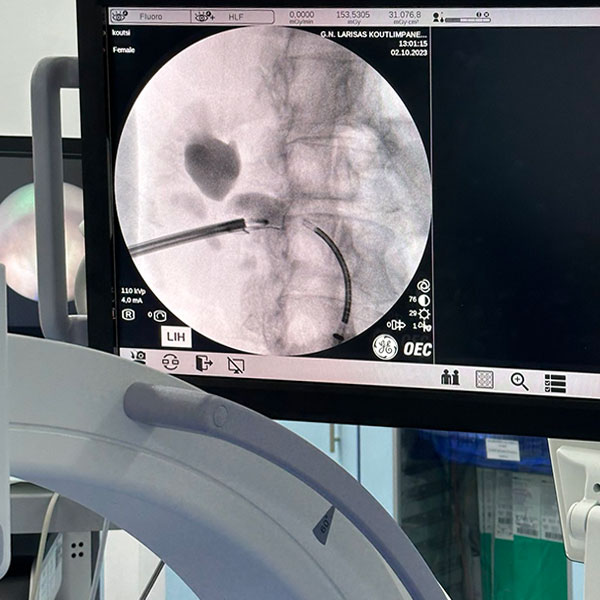

- Διαδερμική νεφρολιθοτριψία

- Εύκαμπτη laser νεφρολιθοτριψία

- Εύκαμπτη laser ουρητηρολιθοτριψία

Επίσης, παρέχει διαδερμική νεφρολιθοτριψία με laser, ουρητηροσκοπική λιθοτριψία με laser, υπερηχοτομογραφικό έλεγχο, εύκαμπτη κυστεοσκόπηση, διορθική βιοψία προστάτη και αναλαμβάνει όλες τις μικροεπεμβάσεις, καθώς επίσης και την αντιμετώπιση της ακράτειας ούρων και τον ουροδυναμικό έλεγχο.